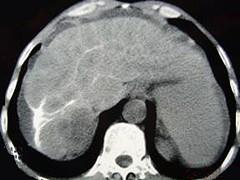

问题 男性,63岁,腹胀、双下肢浮肿、乏力、食欲不振,影像所见如下图,最佳的诊断是 ( )

选项 A.酒精性肝硬化 B.血吸虫肝硬化 C.肝炎后肝硬化 D.局限性脂肪肝 E.原发性肝癌

答案 B